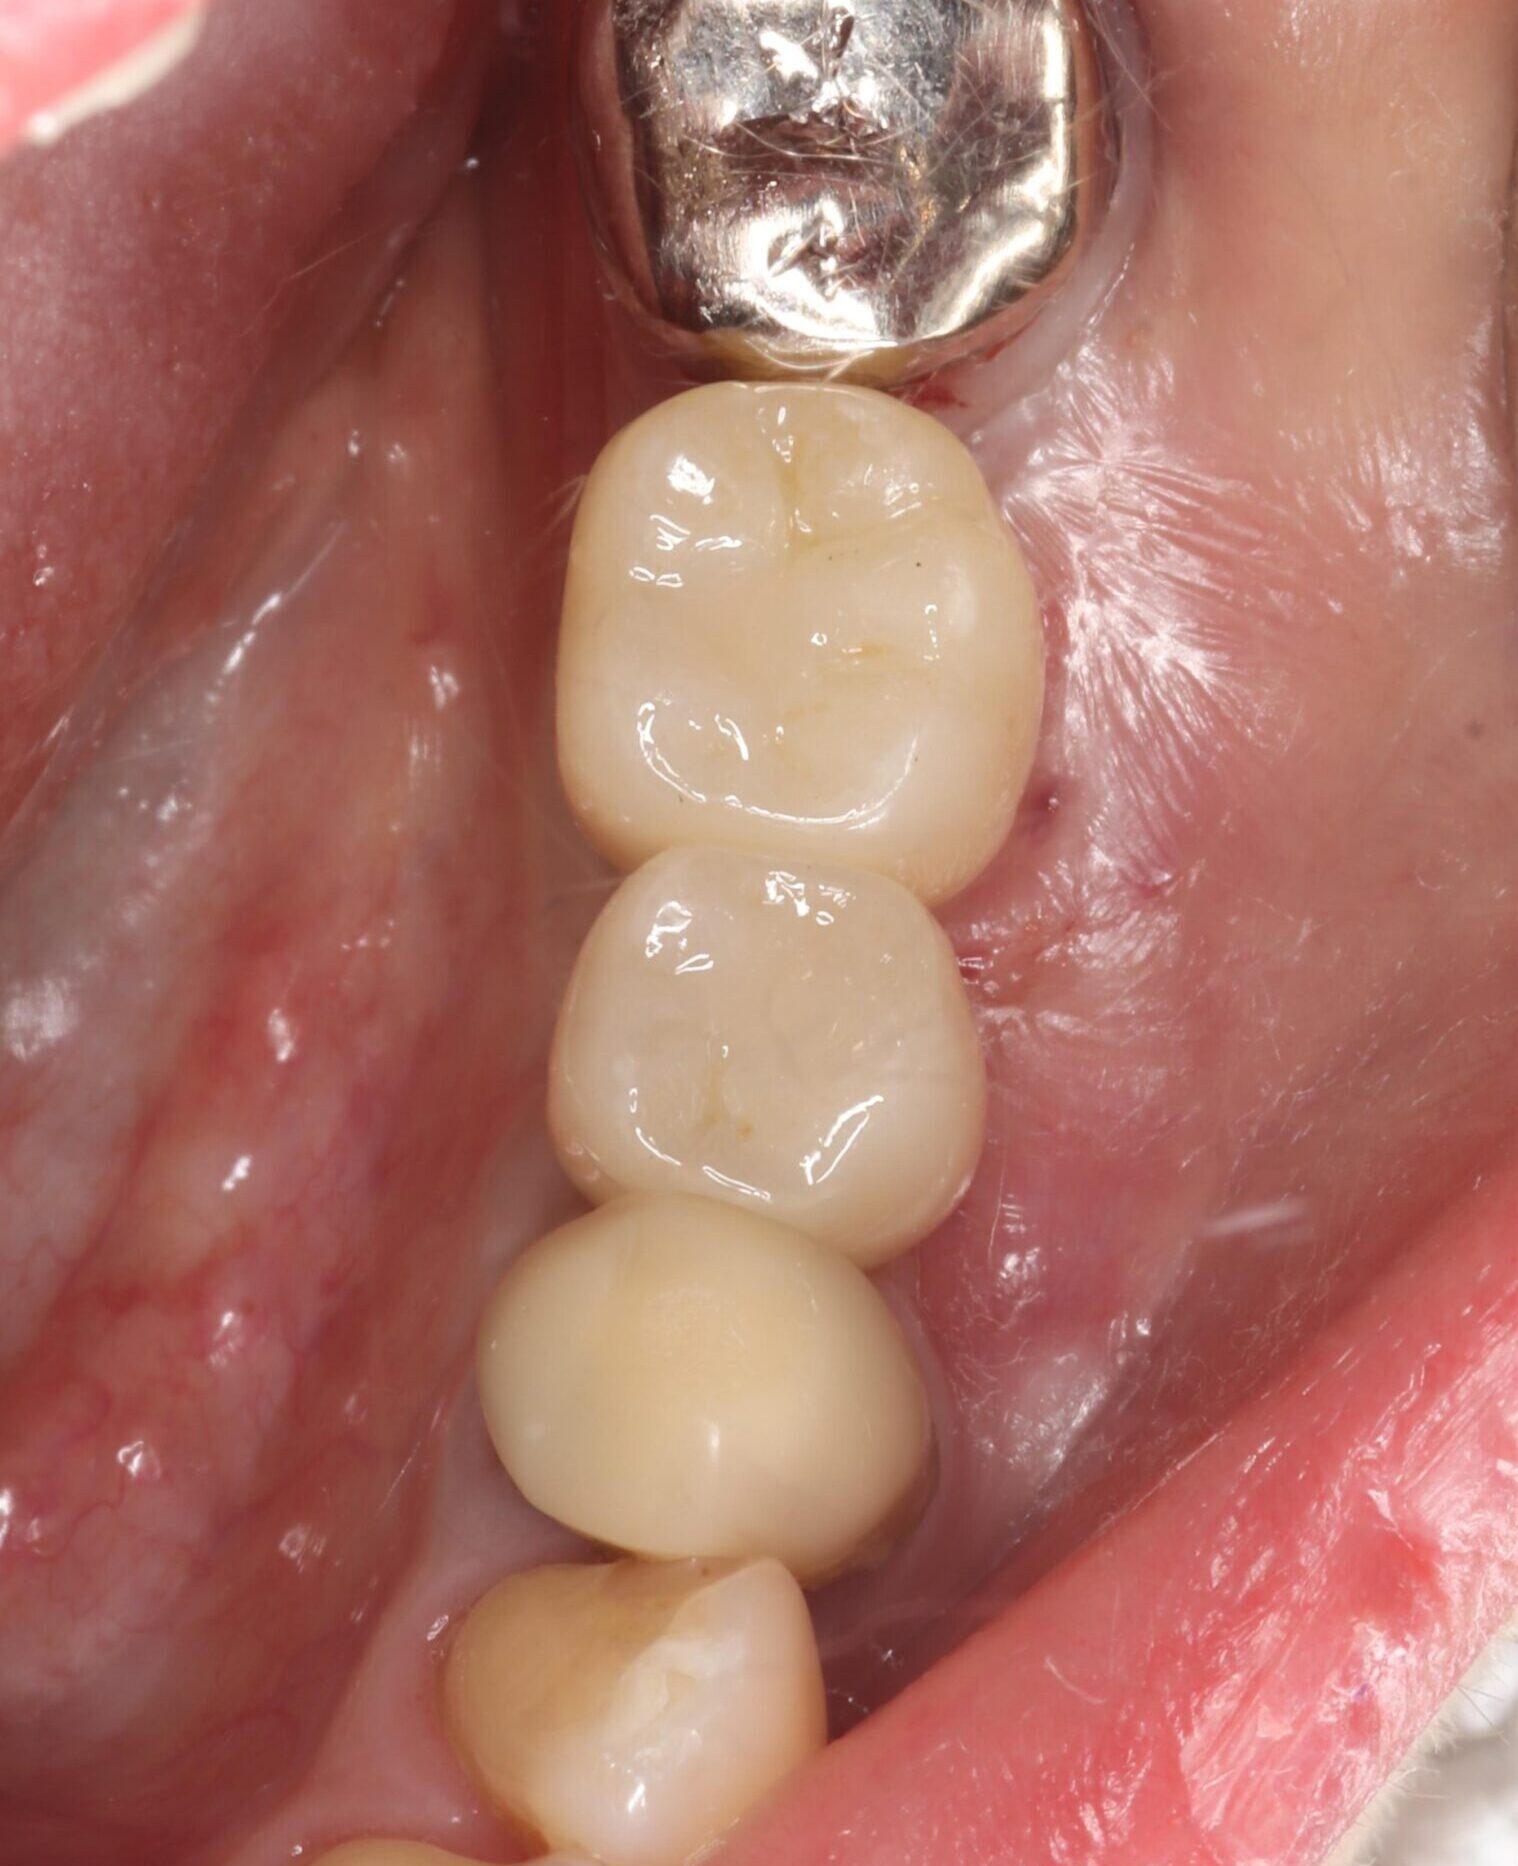

症例02

70代 男性 咬み合わせが強く多くの歯がすぐに壊れる

| 主訴 | 咬み合わせが強く、治療をしてもつくった歯がすぐに壊れる。 他院ではインプラントをいれることも難しいため、断られた。 |

| 年代・性別 | 70代 男性 |

| 治療部位 | 下顎両側 5,6 上顎右側 4 6のインプラントブリッジ ※全顎的に、臨床的歯冠長延長術(クラウンレングスニング)を行い、セラミッククラウンの強度を増しています。 |

| 治療費用 | インプラント 440,000円×6本 |

| 手術回数 | 下顎1回 上顎1回 |

| 治療期間 | 下顎6ヶ月 上顎6ヶ月 |

| 手術時間 | 下顎90分 上顎60分 |

| 治療回数 | 下顎1回 上顎1回 |